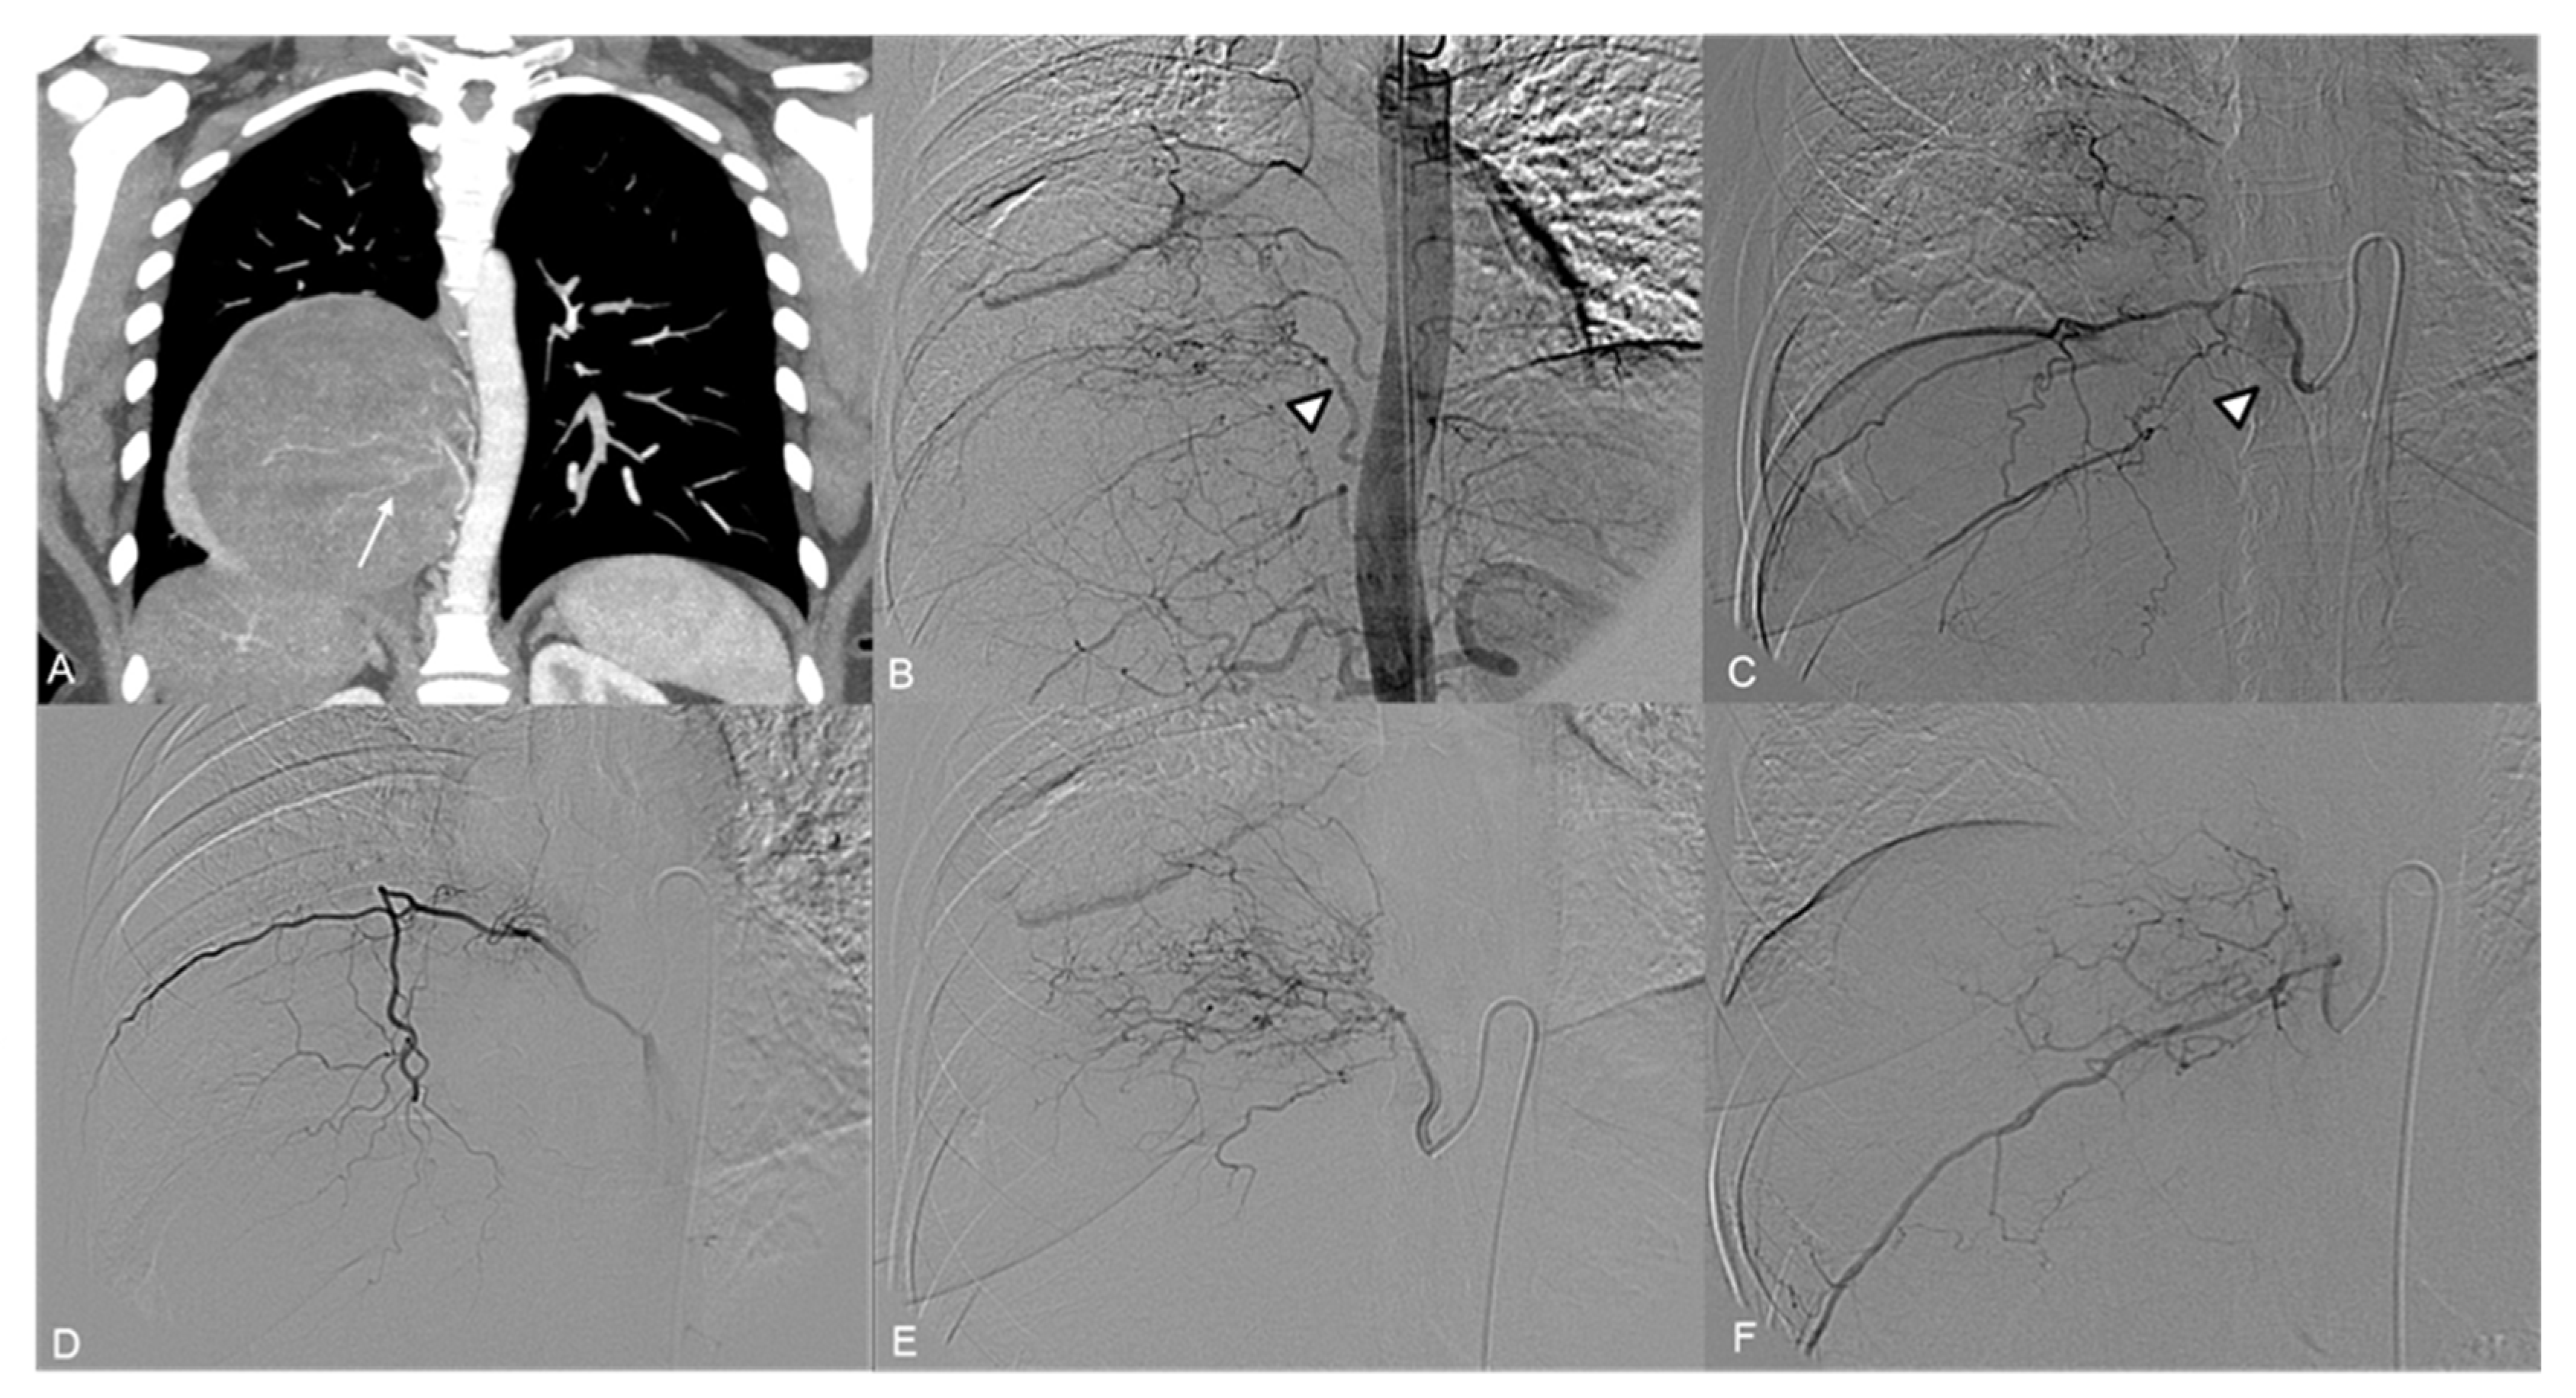

3. Results